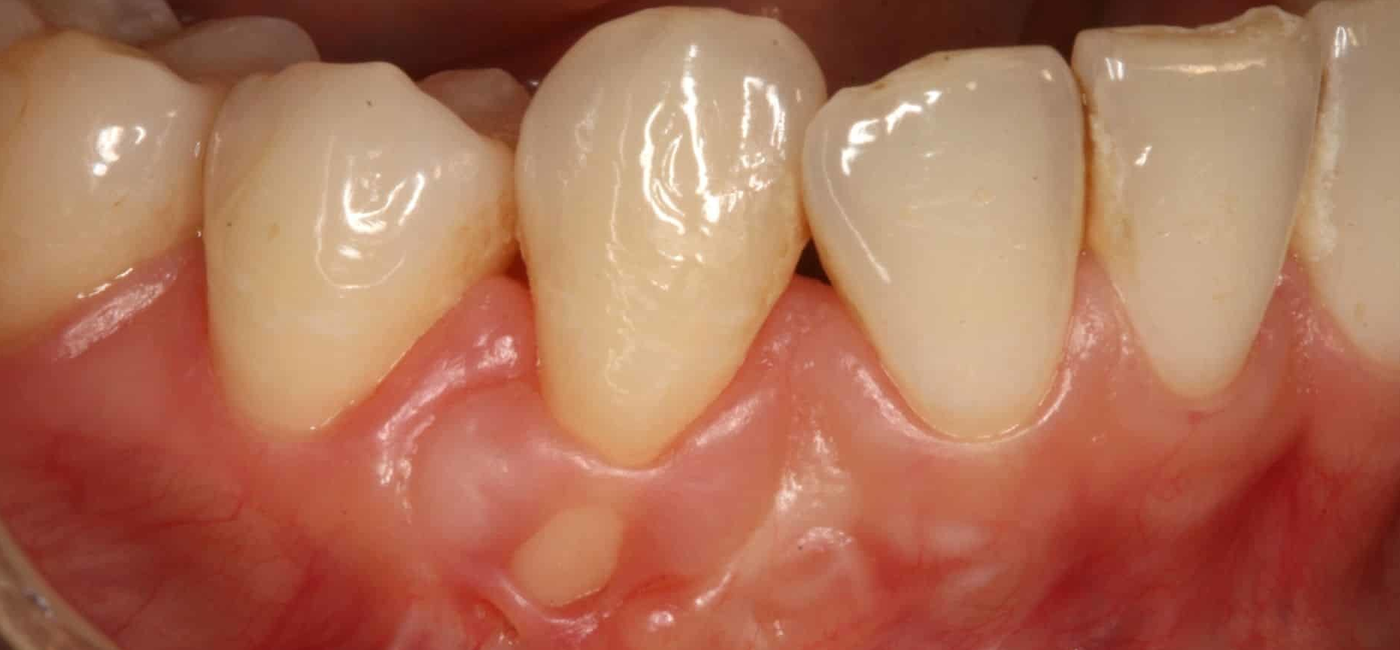

Einjerto de encías, también conocido como injerto gingival, es un procedimiento quirúrgico odontológico que tiene como objetivo restaurar o aumentar el tejido gingival perdido alrededor de uno o varios dientes. Se utiliza principalmente para tratar la recesión gingival, una condición en la que la encía se retrae dejando expuesta parte de la raíz del diente, lo que puede causar sensibilidad, riesgo de caries radicular, problemas estéticos y, en casos severos, pérdida de soporte del diente.

Existen varios tipos de injertos de encía, dependiendo de la necesidad del paciente. El injerto de tejido conectivo es el más habitual y se emplea para cubrir raíces expuestas mediante la toma de una fina capa del paladar. El injerto libre de encía se utiliza para aumentar el espesor del tejido gingival, especialmente en zonas donde la encía es muy delgada. También existen los injertos pediculados, en los que el tejido proviene de una zona cercana al defecto y se traslada manteniendo su irrigación. En algunos casos, se emplean matrices dérmicas o biomateriales, evitando así la necesidad de una segunda zona quirúrgica.

Los beneficios del injerto de encías son notables tanto desde el punto de vista funcional como estético. Este procedimiento protege las raíces dentales expuestas, disminuye la sensibilidad al frío o al calor, detiene el avance de la recesión, facilita una mejor higiene oral y mejora la apariencia de la sonrisa al devolver una línea gingival más natural y simétrica. Además, refuerza la estabilidad de los tejidos blandos alrededor de los dientes o implantes, lo que contribuye a la salud periodontal a largo plazo.